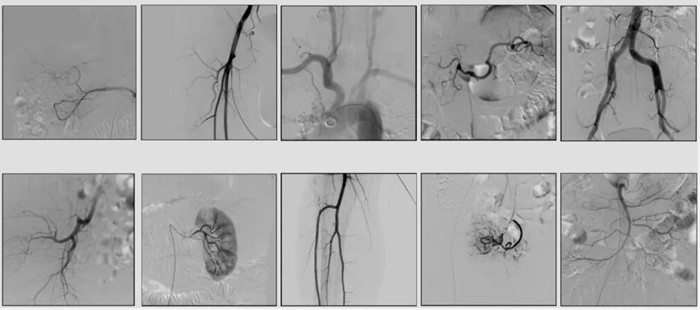

2)中C,學(xué)名外周介入C形臂(Peripheral Interventional C-Arm)。與小C相比,中C不僅大幅提高了X射線系統(tǒng)功率,更重要的是增加了減影等血管機(jī)相關(guān)功能,基本可以完成80%的介入手術(shù)需求,主要應(yīng)用在周圍血管科、消化內(nèi)科、婦科、整形科等領(lǐng)域。

中C在周圍血管領(lǐng)域有重要價(jià)值